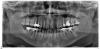

Дмитрий... Опубликовано 29 марта, 2011 Поделиться Опубликовано 29 марта, 2011 Подскажите с чего лучше начать по ремонту зубов и вообще ваше профессиональное мнение .Собираюсь через 2 месяца ставить имплант вверх, а пока что-нибудь подлечить. Ничего не болит,но наверняка есть много проблем. Особенно интересно как дела под старыми коронками . Ссылка на комментарий

Ferny Опубликовано 31 марта, 2011 Поделиться Опубликовано 31 марта, 2011 Справа сверху седьбой зуб с мезиальной стороны не очень понятно есть ли кариес или нет. снизу с левой стороны шестой зуб под мезиальным корнем видно воспаление. Восьмой зуб слева сверху-кариес с мезиальной стороны. Ссылка на комментарий

shishok Опубликовано 1 апреля, 2011 Поделиться Опубликовано 1 апреля, 2011 Большая кариозная полость на медиальной поверхности верхней левой семёрки.Возможно рецидив кариеса на нижней левой пятёрке.(это плюсом ко всему вышесказанному ранее коллегами) Ссылка на комментарий